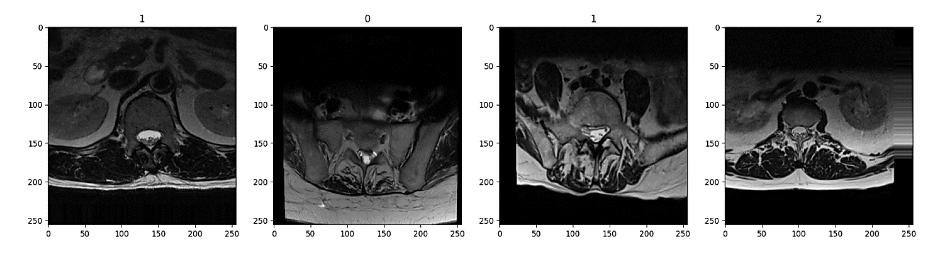

These augmentations effectively increased the representation of underrepresented classes, resulting in a more balanced dataset. Figure 2 shows an example of 4 images of the training dataset, which has been augmented. On the top of the image, it is printed the class that they belong to, following the structure of Table 1. Corresponding 0:Moderate, 1:Normal/Mild, 2:Severe.

Figure 2 – Sample of images with their assigned class after augmentation

Figure 2 shows four sample images after augmentation, each labeled with its assigned class at the top. From left to right, the first image (class 2) appears with minimal tilt. The second image (class 1) is slightly rotated to the right, noticeable in the shift of the spinal structures and the darker region on one side. The third image (also class 1) similarly has a slight rightward tilt, although less pronounced. Finally, the fourth image (class 1) is tilted to the left, and its lower portion appears deeper in the scan, giving a more pronounced sense of depth compared to the others. (one image for pre-augmentation and another post-augmentation)